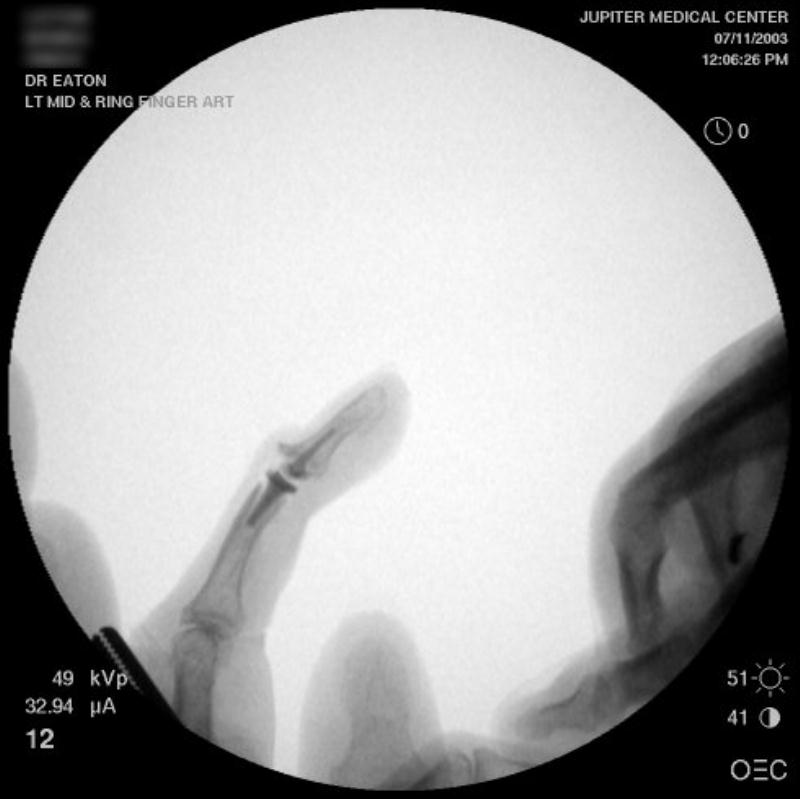

Ring finger DIP joint of the opposite hand.

Intraoperative fluoroscopy using the same technique as above. The trial spacers:

The final implant: